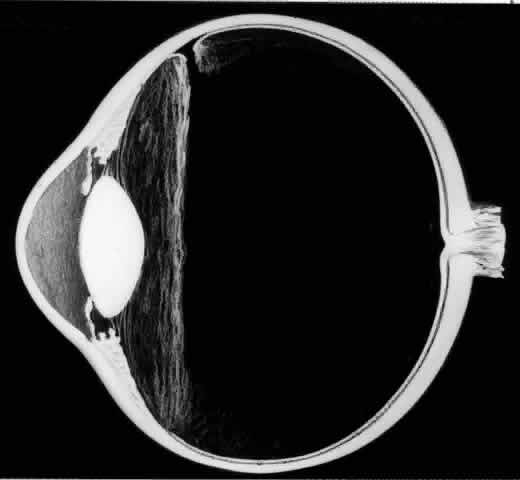

The earliest biomicroscopic changes preceding the development of a giant retinal tear were syneresis and liquefaction of the vitreous gel, converting the posterior and central portions of the vitreous body into a large lacuna (Fig. 14). Later, the anterior gel became condensed, and its posterior aspect formed an equatorially oriented membrane extending across the vitreous cavity (Fig. 15). This membrane did not oscillate with ocular movements, suggesting that it was under tension. Marked contraction of this membrane seems responsible for tearing the retina along the posterior border of the vitreous base (Fig. 16). Liquefied vitreous gel facilitated inversion of the posterior retinal flap (Fig. 17).

Fig. 16. Contraction of this equatorially oriented membrane extending across the vitreous cavity produces a giant tear along the posterior border of the vitreous base.

Fig. 17. After the formation of a giant retinal tear, the posterior retinal flap inverts into the liquefied vitreous (arrow).